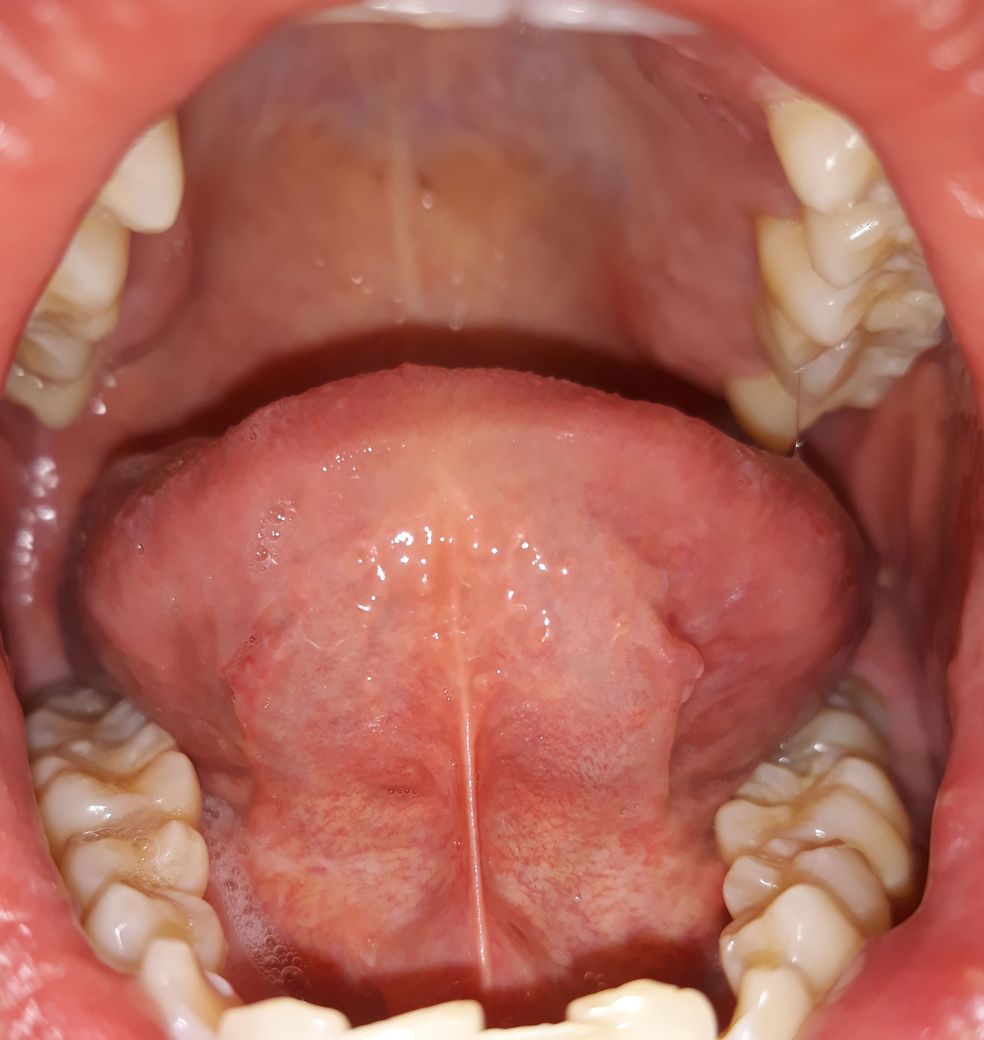

혓바닥 아래 상태가 정상인가요???

양치하다가 혓바닥 옆쪽 아래를 봤는데 잔핏줄도 많이 보이고 중간에 색깔도 군데군데 누런거같기도한데 만져보니깐 부드럽고 통증이나 불편한건 없습니다. 괜찮은건가요?

• 4번 째 사진

입 구석구석을 살펴보셨네요. 사진 올려주신 것만 봐서는 특별한 이상은 없어 보입니다. 증상도 없으니 괜찮다고 보셔도 되구요.

특별히 현재 통증 및 이물감 등이 있는 것이 아니라면 이상소견으로 보지는 않습니다.

만약 증상발생시는 치과에 내원해 보시는 것을 추천드립니다.